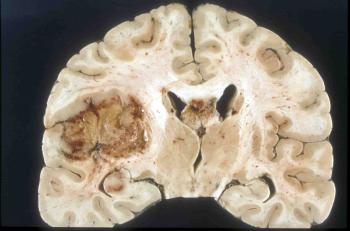

Глиобластома, рак головного мозга, является наиболее агрессивной и распространенной среди опухолей такой локализации. Особенности течения заболевания по стадиям, его симптомы, а также способы профилактики и прогнозы выживаемости - вот ключевые пункты, интересующие пациентов, столкнувшихся с таким недугом. Поэтому следует подробнее остановиться на рассмотрении этих аспектов.

Этот вид опухоли мозга не только самый агрессивный, но и самый распространенный. Около 52% первичных опухолей головного мозга являются именно глиобластомами.